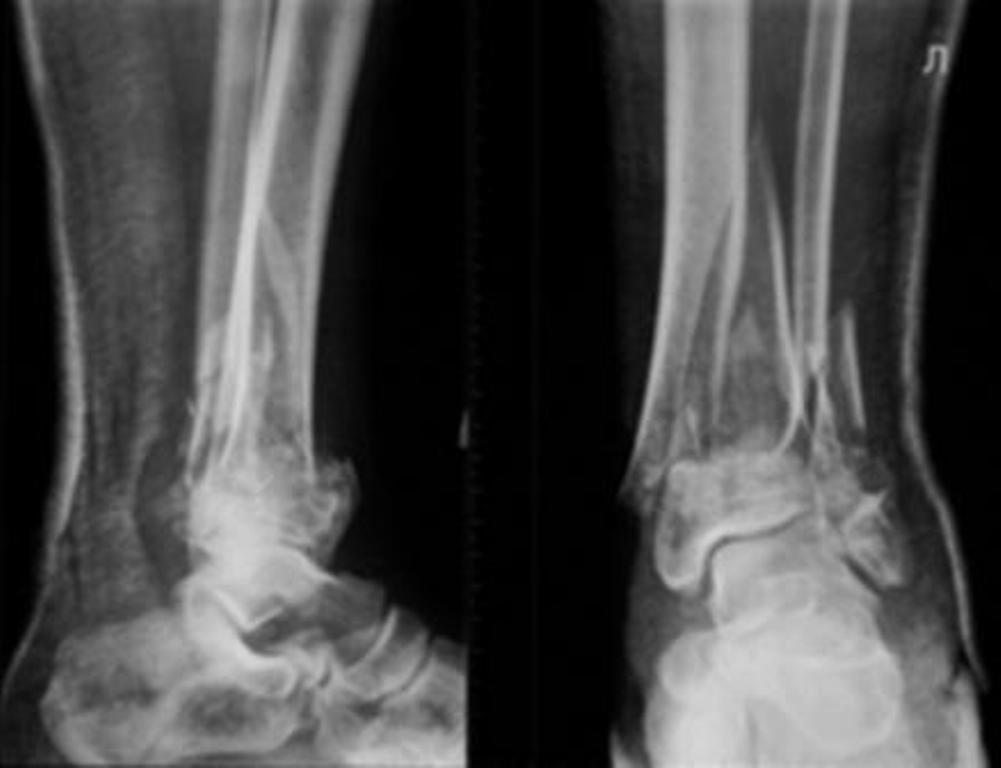

[Ortho] Перелом дистального отдела костей голени

До лечения, в процессе, через 8 мес.